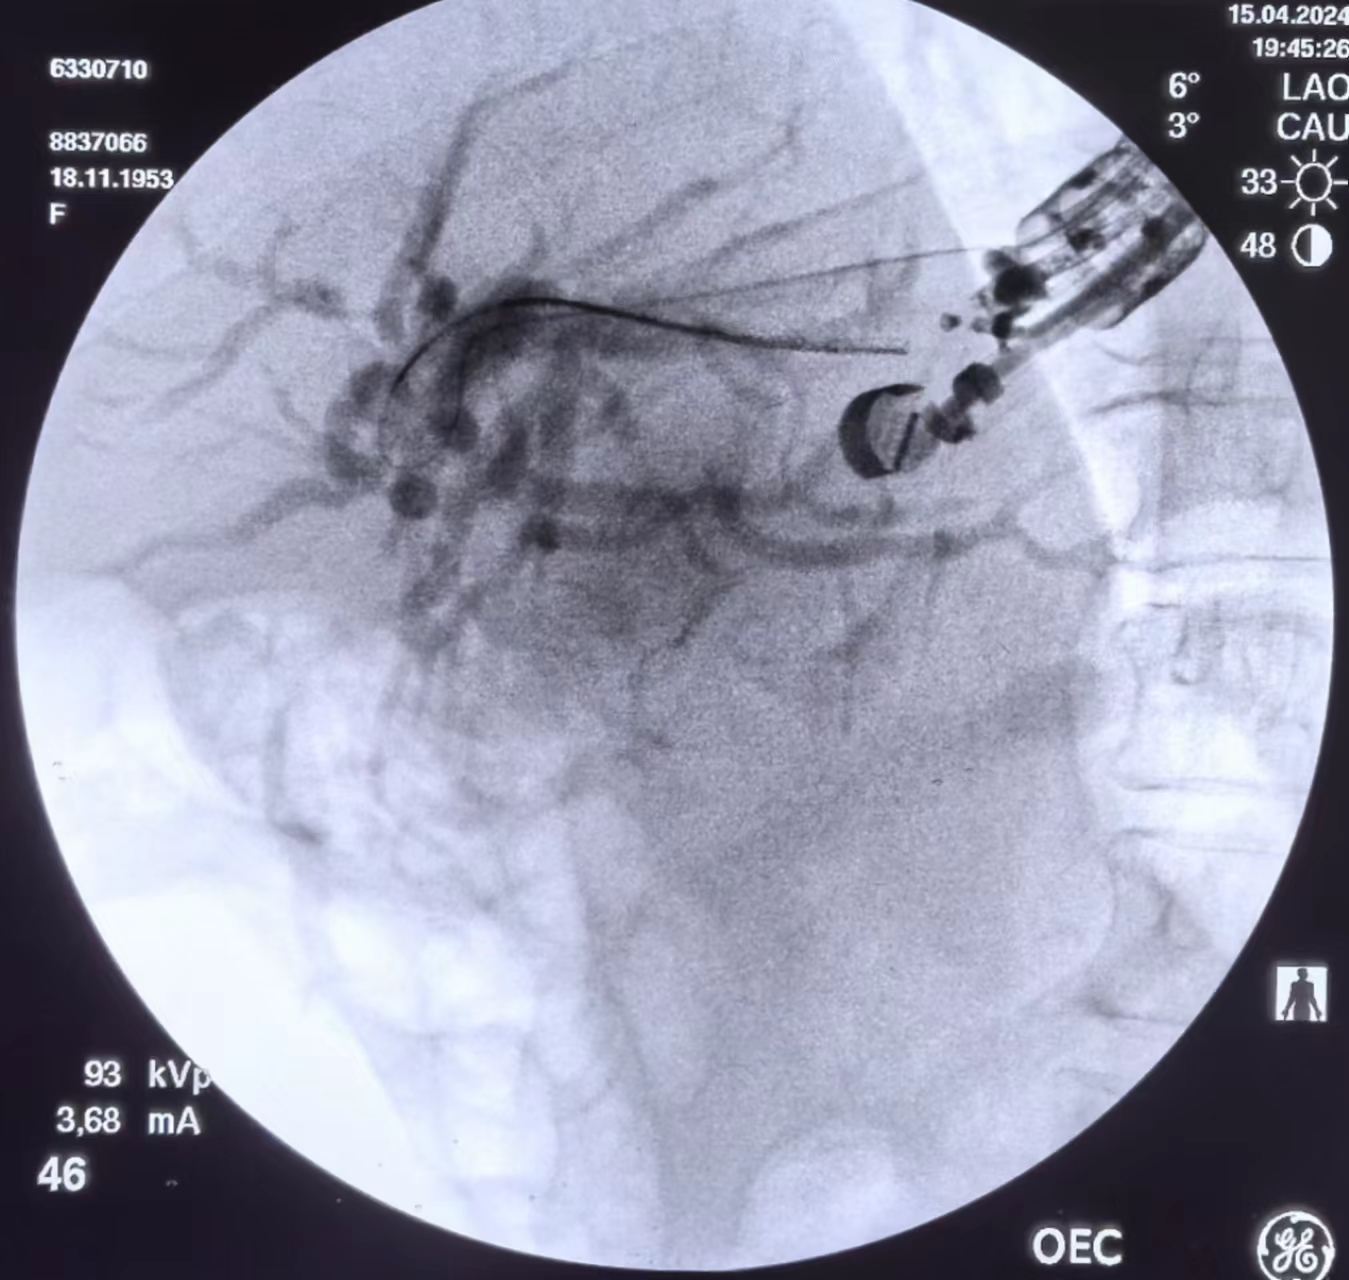

分享一例EUS-BD,向大家汇报一下

下图为患者部分手术图像

置入搭桥支架(相当于HGS+AS)